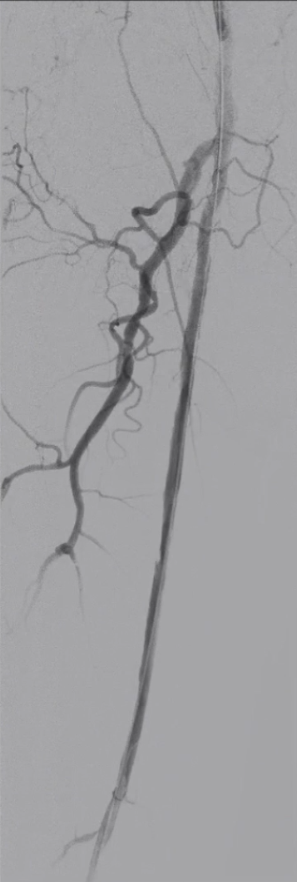

造影确认病变:长段闭塞,流出道尚可

造影显示右侧股动脉自起始段起长段闭塞,远端腘动脉及膝下动脉经股深侧枝显影,流出道条件尚可,为手术提供了基础。